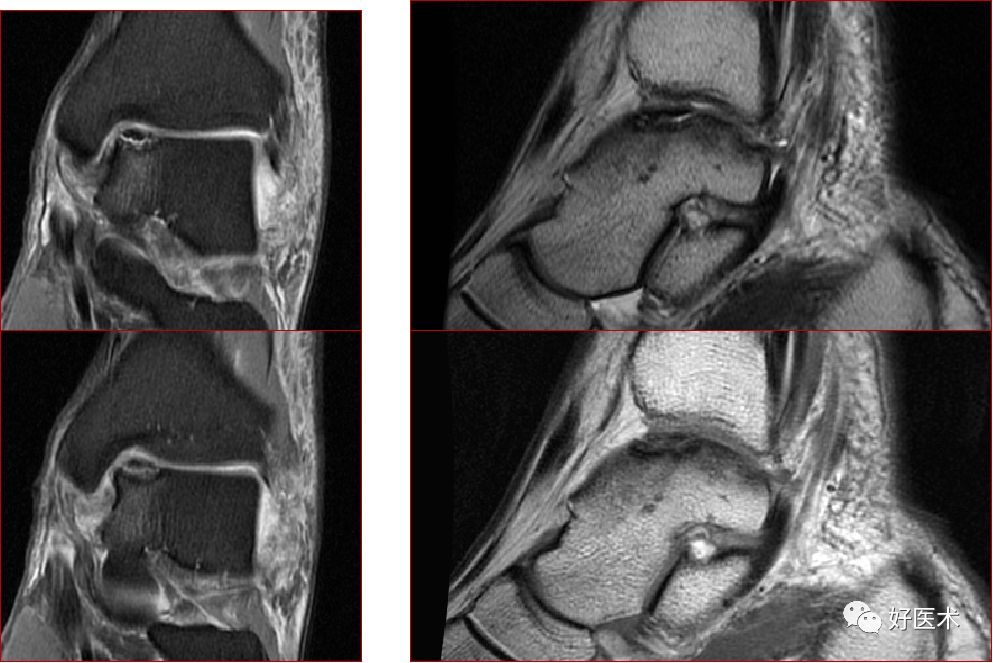

三、骨软骨病变

距骨骨软骨损伤,好发于前外侧、后内侧,尤其是后内侧,与内外翻损伤相关。

距骨骨软骨损伤分级

1度损伤:

2度损伤

3度损伤